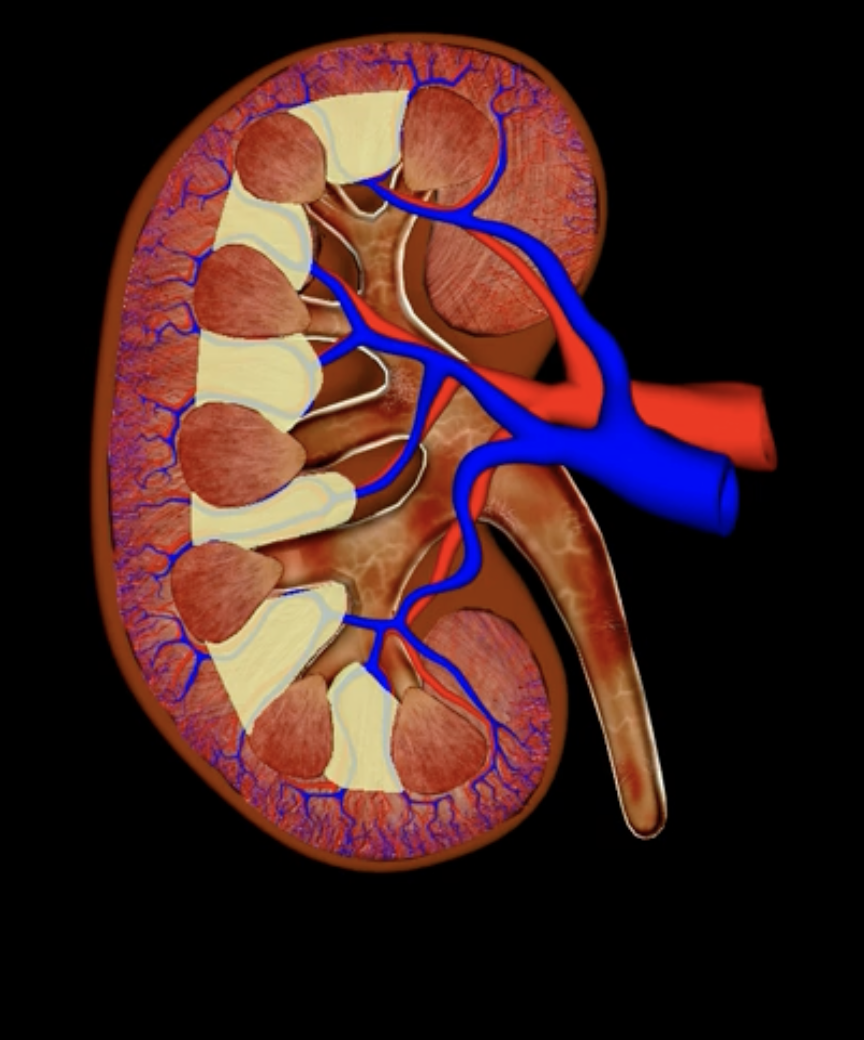

renal cortex

green

renal medulla

blue

renal columns

yellow

renal pyramids

purple

renal lobe

orange

renal papilla

minor calyx

teal

major calyces

renal pelvis

minor and major calyces